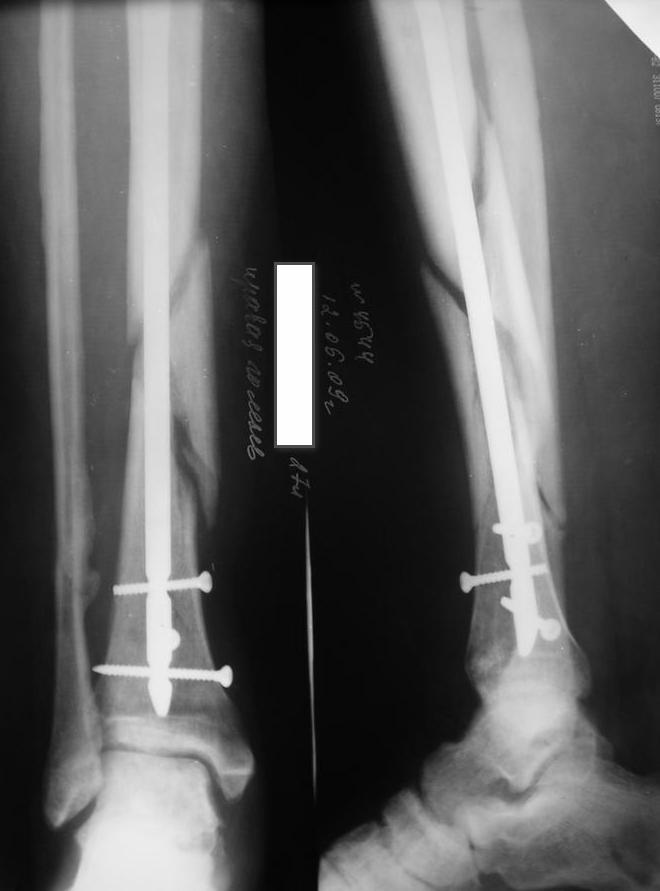

Уважаемые коллеги травматологи подскажите как нам быть и что делать. Думали всем

отделением.Несрощение оскольчатого перелома костей голени после интрамедуллярного

блокируемого синтеза.

операции пациент ходил с полной нагрузкой. Через 3 месяца на контрольных рентгенограммах

сращения нет, динамизации не выполняли, так как оскольчатый перелом.(снимки в динамике

прилагаются). Посоветуйте, что в данном случае делать наиболее целесообразно?